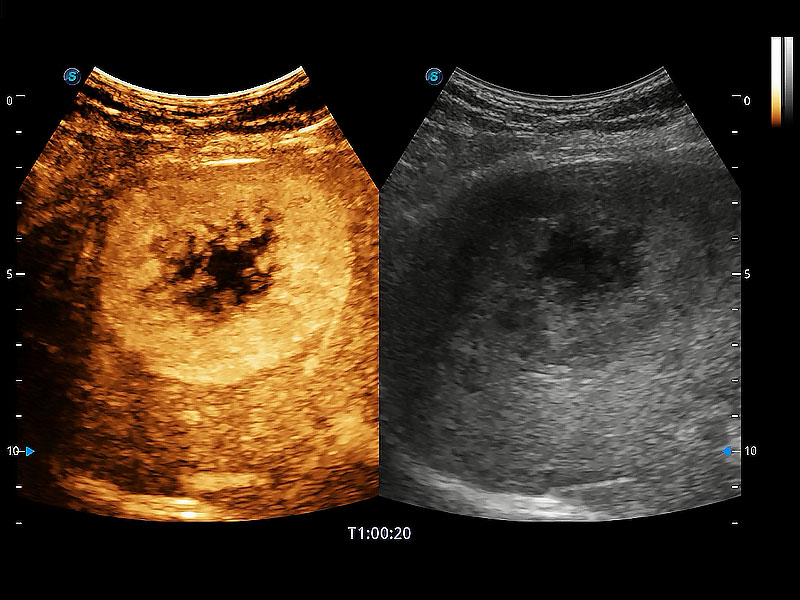

高性能和先进的临床应用工具可以为动物医生提供临床信心。ProPet 80 搭载了先进的腹部和浅表应用工具,帮助医生在日常临床实践中发挥前所未有的作用。

非线性融合造影成像充分利用谐波和基波信号,为难以观察的血流进行增强显像。可用于线阵、凸阵、微凸阵、相控阵探头。

ProPet 80 全新的动物超声智能软件和丰富的探头群,为动物医生提供了高清晰度和精细分辨率的图像,无论在宠物、马科、畜牧还是实验室动物等应用中都可以轻松应对,为您的日常工作带来满意的体验。